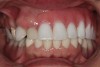

A 63-year-old woman presented with upper and lower partial dentures (Figure 1). She had become frustrated with the lack of stability of the partials and the failing abutment restorations. She was also concerned about her appearance. The patient’s present health condition was documented, which included arthritis, chronic lower back pain, chronic narcotic use, and hepatitis. The patient was presently on a regimen of Celebrex, Fiorcet, and oxycodone. It was also noted that the patient had an allergy to codeine.

Figure 1  Preoperative retracted image of the patient’s dentition.

Figure 1